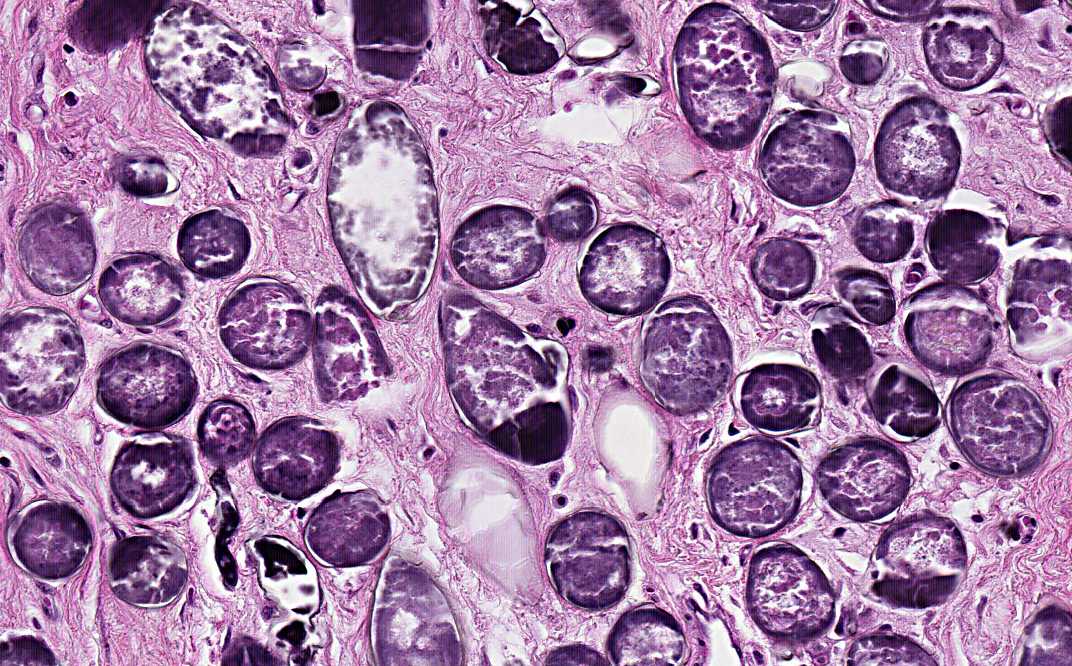

Hematoxylin & eosin

Area 2: The calcified eggs caused substantial fibrosis.

• The more interesting lesion, however, is featured by numerous round to olive shaped structure with a calcified shell. These organisms are the calcified eggs of Schistosoma.